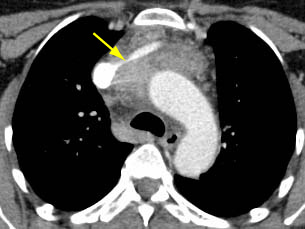

Tomografia computadorizada (TC) do tórax mostrando timoma com encarceramento e invasão da veia inominada esquerda

Do acervo de Cameron Wright, MD; usado com permissão